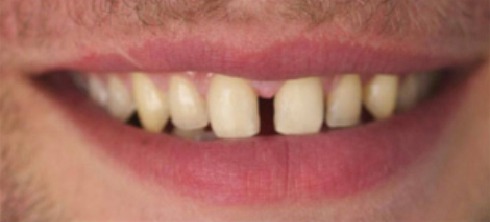

Crowding and constricted arch. Comprehensive orthodontic treatment was performed, and teeth alignment was restored.